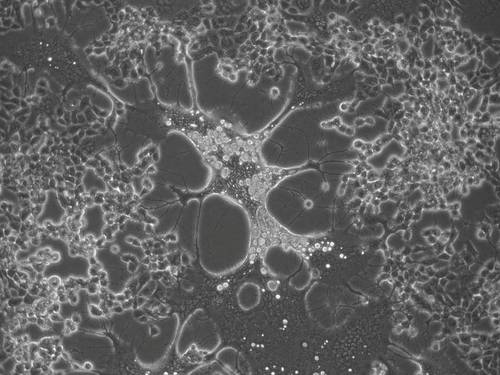

El virus del herpes genital humano evoluciona más rápido que el labial

Un estudio del CSIC muestra que el virus del herpes simple, uno de los patógenos humanos más prevalentes y para el que no hay cura ni vacuna, acumula cambios al replicarse. Este conocimiento podría servir para desarrollar antivirales.